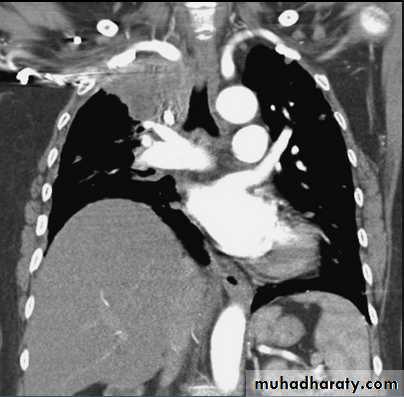

Massive pleural effusion with mediastinal shift to the left.

(A) Chest radiograph(B) CT coronal reconstruction. A massive effusion displaces the mediastinum to the left. CT shows the important pleural effusion together with the enhanced atelectatic left lung.

Note also the depression of the right hemidiaphragm (arrows).